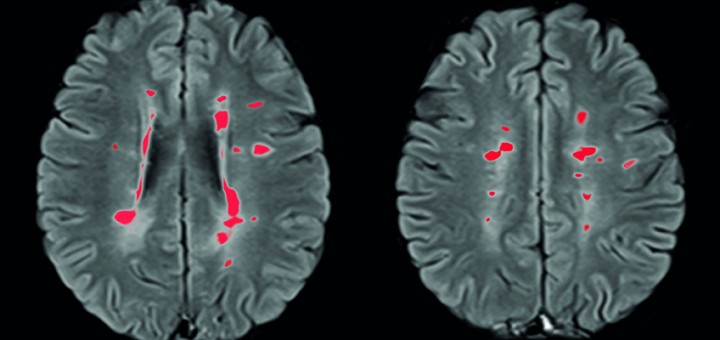

Ma cosa succede quando il sistema immunitario pensa che il tuo sistema nervoso sia nemico e attacca il tuo corpo? Questa risposta autoimmune è la triste realtà di chi è affetto da sclerosi multipla (SM).

La SM è una malattia debilitante che colpisce milioni di persone in tutto il mondo. Comporta paralisi progressiva, dolore, compromissione della memoria, della vista e spesso provoca la morte. Il Canada ha il più alto tasso di SM nel mondo. Il motivo di questo alto tasso di sclerosi multipla non è noto.

A differenza dei fili di casa, questo isolamento è realizzato con un materiale grasso chiamato mielina. Nella SM, questa guaina mielinica viene distrutta, lasciando scoperte le connessioni neurali. Ciò comporta che i neuroni non riescono a inviare segnali, portando a paralisi ed eventuale morte.